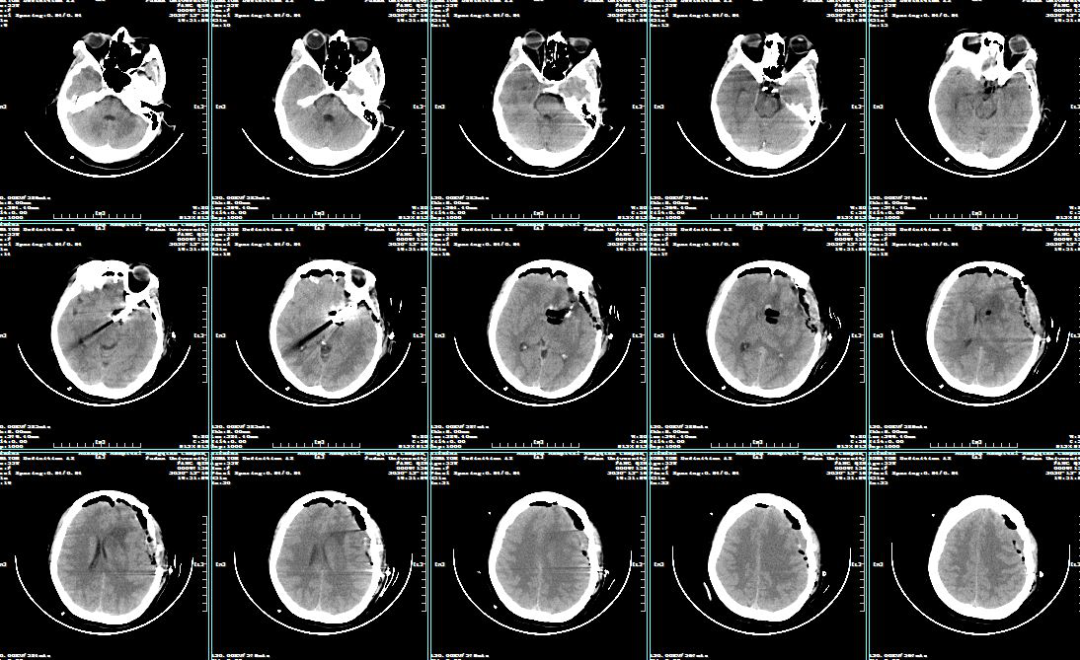

2020-12-16 post-op CT

术中电生理未见明显异常,因此未进行进一步血流重建处理。